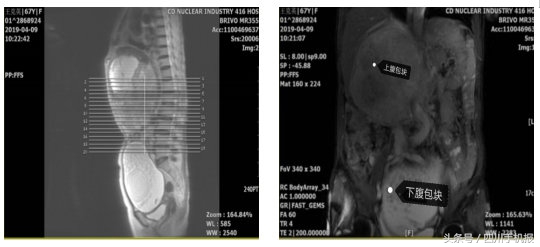

她的上腹右肋下、下腹盆腔内各有一处包块,大小分别约20cm、16cm,最大那个已经十分接近标准足球的大小。

这两个家伙在她的肚子里看似安分,但无时无刻不挤压着她的肠管、肝脏、胰腺、右肾等等器官。

(血管造影显示:右侧肾脏血管受压,血流几乎阻断)